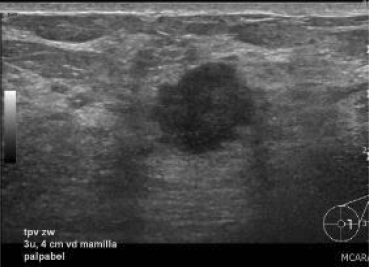

Figuur 2

Echografische afbeelding van een irregulaire onscherp begrensde massa links lateraal van de tepel. Op basis van de vorm en begrenzing moet deze massa worden verslagen als verdacht voor maligniteit, BI-RADS 4 (pathologie: invasief ductaal carcinoom).